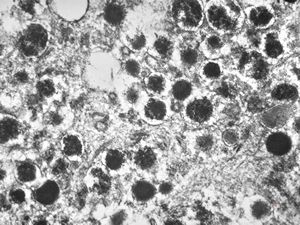

M, 38y. | pheochromocytoma